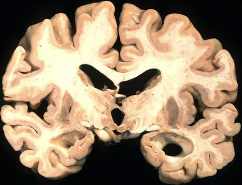

Los altos niveles de hierro en la sangre pueden llevar a la producción de radicales libres capaces de dañar las neuronas en su cerebro. También se cree que el hierro se acumula en altos niveles, y es extremadamente reactivo en las placas de beta-amiloide que se encuentran en el cerebro de los pacientes con Alzheimer.

También se sabe que el hierro se acumula específicamente en las regiones del cerebro asociadas con los procesos de la memoria y el pensamiento, que se pierde gradualmente a medida que progresa la enfermedad de Alzheimer. En este momento no es del todo claro saber si el exceso de hierro es el resultado de fuentes externas, como los suplementos o sartenes de metal, o debido a una predisposición genética que permite el exceso de hierro o por cambios bioquímicos que causan un desequilibrio interno; probablemente es una combinación de todos.

Lo que se sabe es que el exceso de hierro en áreas donde no debe estar es claramente tóxico, y cuando se acumula en las neuronas podría ser la “etapa final de la neurodegeneración»4.